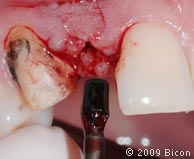

29. Удаление излишков мягких тканей, которые могут препятствовать правильной установке трансфера, производится посредством слепочного римера размером 3 мм, вращаемого вокруг направляющего штифта.

30. Коронка, зацементированная на правом клыке.

31. Подрезка зеленого 3,0 мм трансфера – эта операция позволит избежать соприкосновения с соседними зубами, которое может изменить траекторию движения аналога.

32. Установка пластикового слепочного трансфера в имплантат.

33. Досаживание трансфера после цементирования коронки на левом верхнем клыке.

34. Нанесение слепочной массы вокруг трансферов и снятие слепка по уровню имплантата.